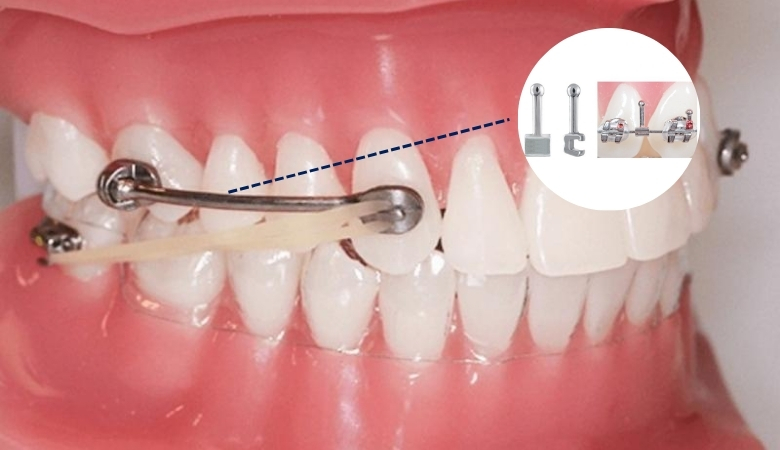

Đóng khoảng bằng móc kéo (hook)

Đây là phương pháp phổ biến trong niềng răng mắc cài, sử dụng các móc (hook) được gắn trên mắc cài kết hợp với dây cung để tạo lực kéo giữa các răng.

Cơ chế hoạt động của phương pháp này là bác sĩ sẽ gắn móc vào vị trí phù hợp, sau đó dùng lực từ dây cung hoặc kết hợp với các khí cụ khác để kéo răng dịch chuyển dọc theo cung hàm. Ưu điểm của phương pháp này là dễ điều chỉnh răng linh hoạt theo từng giai đoạn điều trị. Tuy nhiên, có thể gây cảm giác khó chịu và vướng víu khi các móc kéo ma sát với niêm mạc miệng. Đây là một trong những nguyên nhân gây ra lở miệng khi niềng.

Đóng khoảng bằng móc kéo (hook)

Đóng khoảng bằng chun chỉnh nha

Chun chỉnh nha là một trong những phương pháp hỗ trợ đóng khoảng quen thuộc, được sử dụng để tạo lực kéo giữa các răng hoặc giữa hai hàm. Với phương pháp này, chun sẽ được gắn vào các móc trên mắc cài để kéo các răng lại gần nhau, giúp thu hẹp khoảng trống nhanh hơn.

Đóng khoảng bằng chun chỉnh nha

Tuy nhiên, hiệu quả của việc đóng khoảng bằng chun chỉnh nha phụ thuộc rất lớn vào sự hợp tác và kiên trì của người niềng. Nếu không đeo đủ thời gian, tháo ra thường xuyên hoặc đeo sai vị trí, lực kéo sẽ không ổn định, dễ làm kéo dài thời gian điều trị hoặc ảnh hưởng đến khớp cắn.